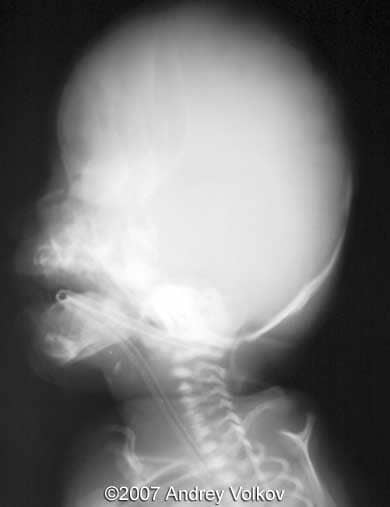

The diagnosis of Pfeiffer syndrome (type II) was proposed. The neonate was delivered at 32nd week after premature rupture of membranes (1800 g; 39 cm; Apgar 1, 3) and died early after delivery. Pathological study confirmed the diagnosis.

Images 7, 8: Postnatal X ray images of the skull; Image 7 shows cloverleaf shaped appearance of the skull.